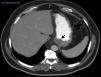

The CT result was negative in 253 cases (81.61%). A total of 72 incidentalomas were identified in 56 scans (18.06%). One scan (0.32%) performed on a patient with a stage T3a CM revealed an image that was suggestive of isolated liver metastasis, which was later confirmed after resection (Fig. 2). The most commonly detected incidentalomas were space-occupying lesions in the liver (19[26.39%]), followed by solitary pulmonary nodules (11[15.28%]) (Fig. 3). A total of 35 incidentalomas (48.61%) were classified as not relevant, whereas 37 (51.39%) were studied further (Fig. 4). In 2 cases (0.64%), the incidentalomas were adenocarcinoma of the stomach and lung carcinoma (Fig. 5). Three of the CT scans (0.97%) were relevant in oncological terms (1 patient with metastasis of melanoma and 2 patients with a second primary tumor).

There are no studies on incidentalomas during staging of melanoma, probably because there is no reason for the frequency of incidentalomas in patients with melanoma (18.06% in the present series) to differ from that of the general population. However, the frequent space-occupying lesions observed in the liver (26.39%) and lungs (22.22%, solitary and multiple pulmonary nodules), which are common sites of metastatic melanoma, necessitate additional tests to rule out metastasis. With respect to second tumors, those identified in the present study (1 lung cancer in a 77-year-old smoker with stage T4b disease and a 60-year-old patient with melanoma in situ and gastric adenocarcinoma) do not allow us to make recommendations on the benefit of staging CT in the diagnosis of second tumors.